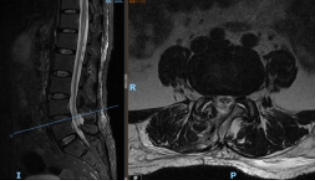

术前 MR 术后 MR